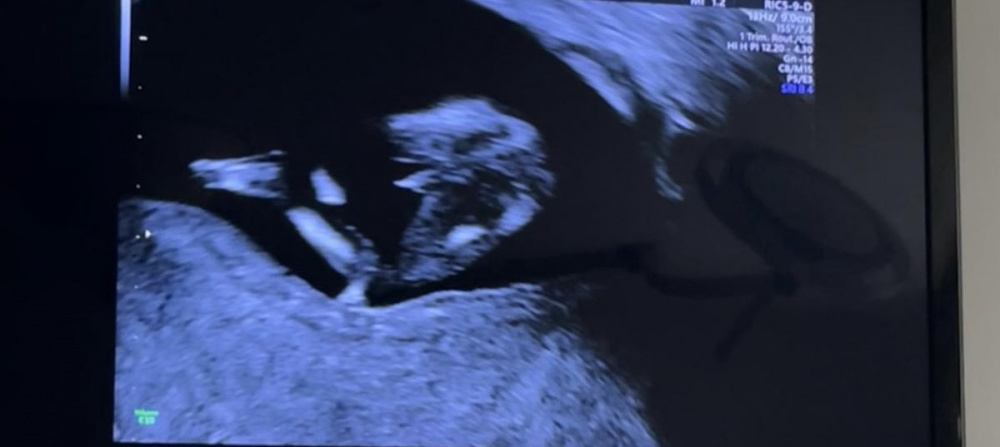

Eindeutig Junge ? 12+5

Hatte gestern bei 12+5 das ETS. Ärztin wollte uns nicht verraten, aber sieht das nicht eindeutig aus ? Oder könnte da evt. Die Nabelschnur oder etwas anderes im Weg sein :)